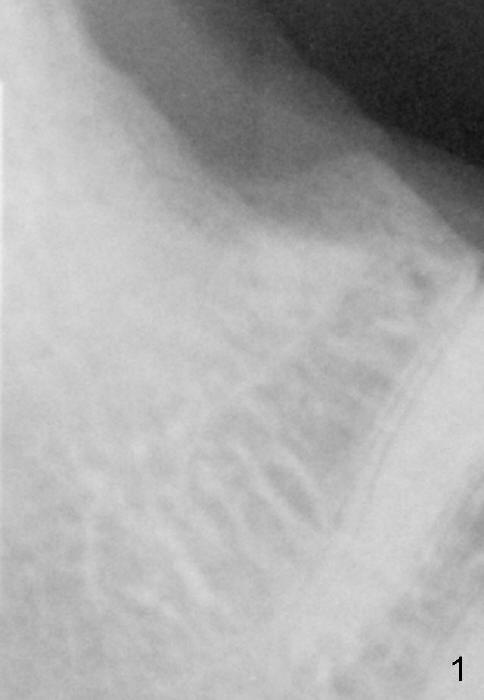

Fig.1: Approximately two months post extraction